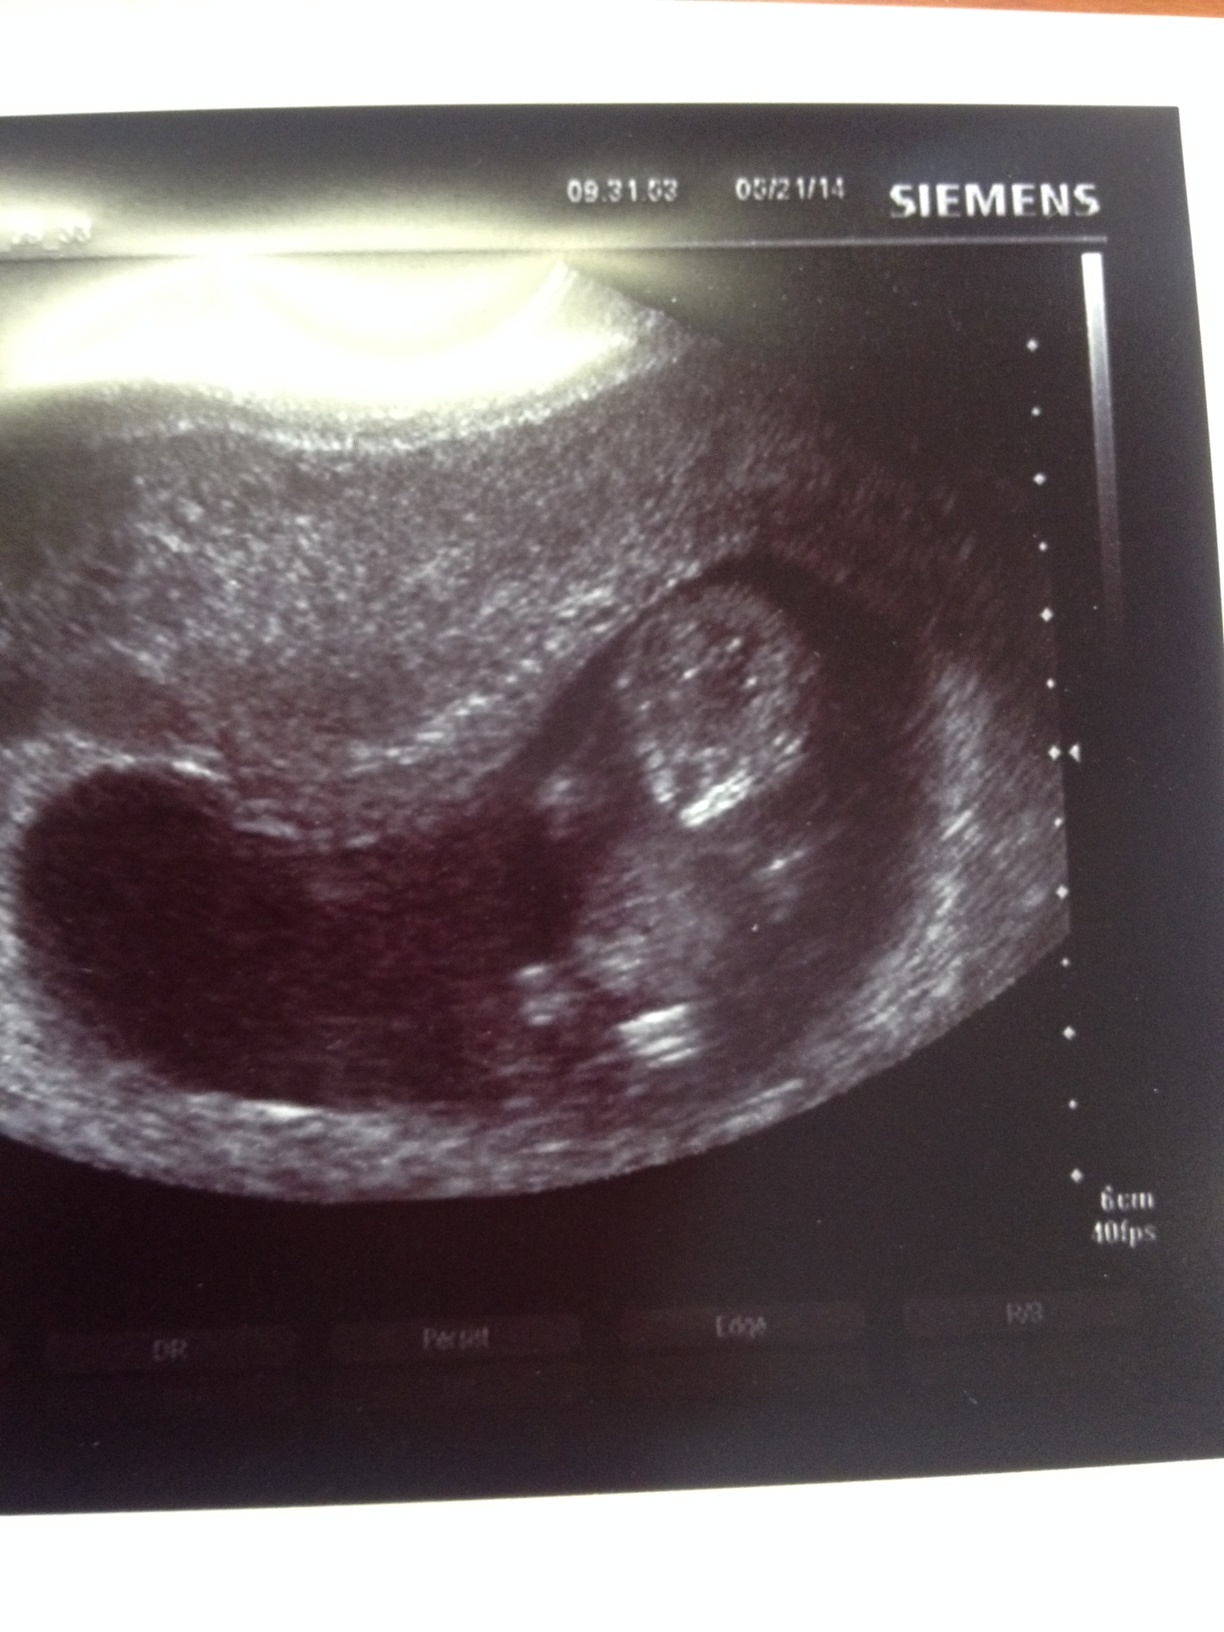

I had a consult on Monday with my OB office and went back in yesterday for a meeting with the midwife (I chose midwife care over OB care) and I had an ultrasound. I'm so glad that I chose to go with midwife care - I left the office feeling super positive, all of my questions were answered, I wasn't rushed through my appointment, and I felt confident and comfortable with my choice of trying to have a natural birth.

Here's a picture from yesterday of my little bean. I'm amazed that I have this perfect little human growing in my belly. I'm so thankful and blessed.